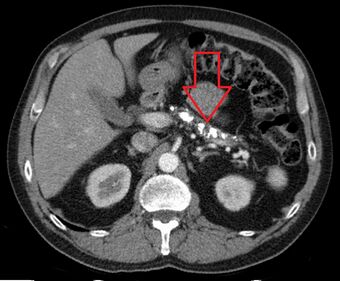

| Axial CT showing multiple calcifications in the pancreas in a patient with chronic pancreatitis |

A biopsy of the pancreas is not required for the diagnosis.[4] On imaging, pancreatic and bile duct dilatation, atrophy of the pancreas, multiple calcifications of the pancreas, and enlargement of pancreatic glands can be found.[12]